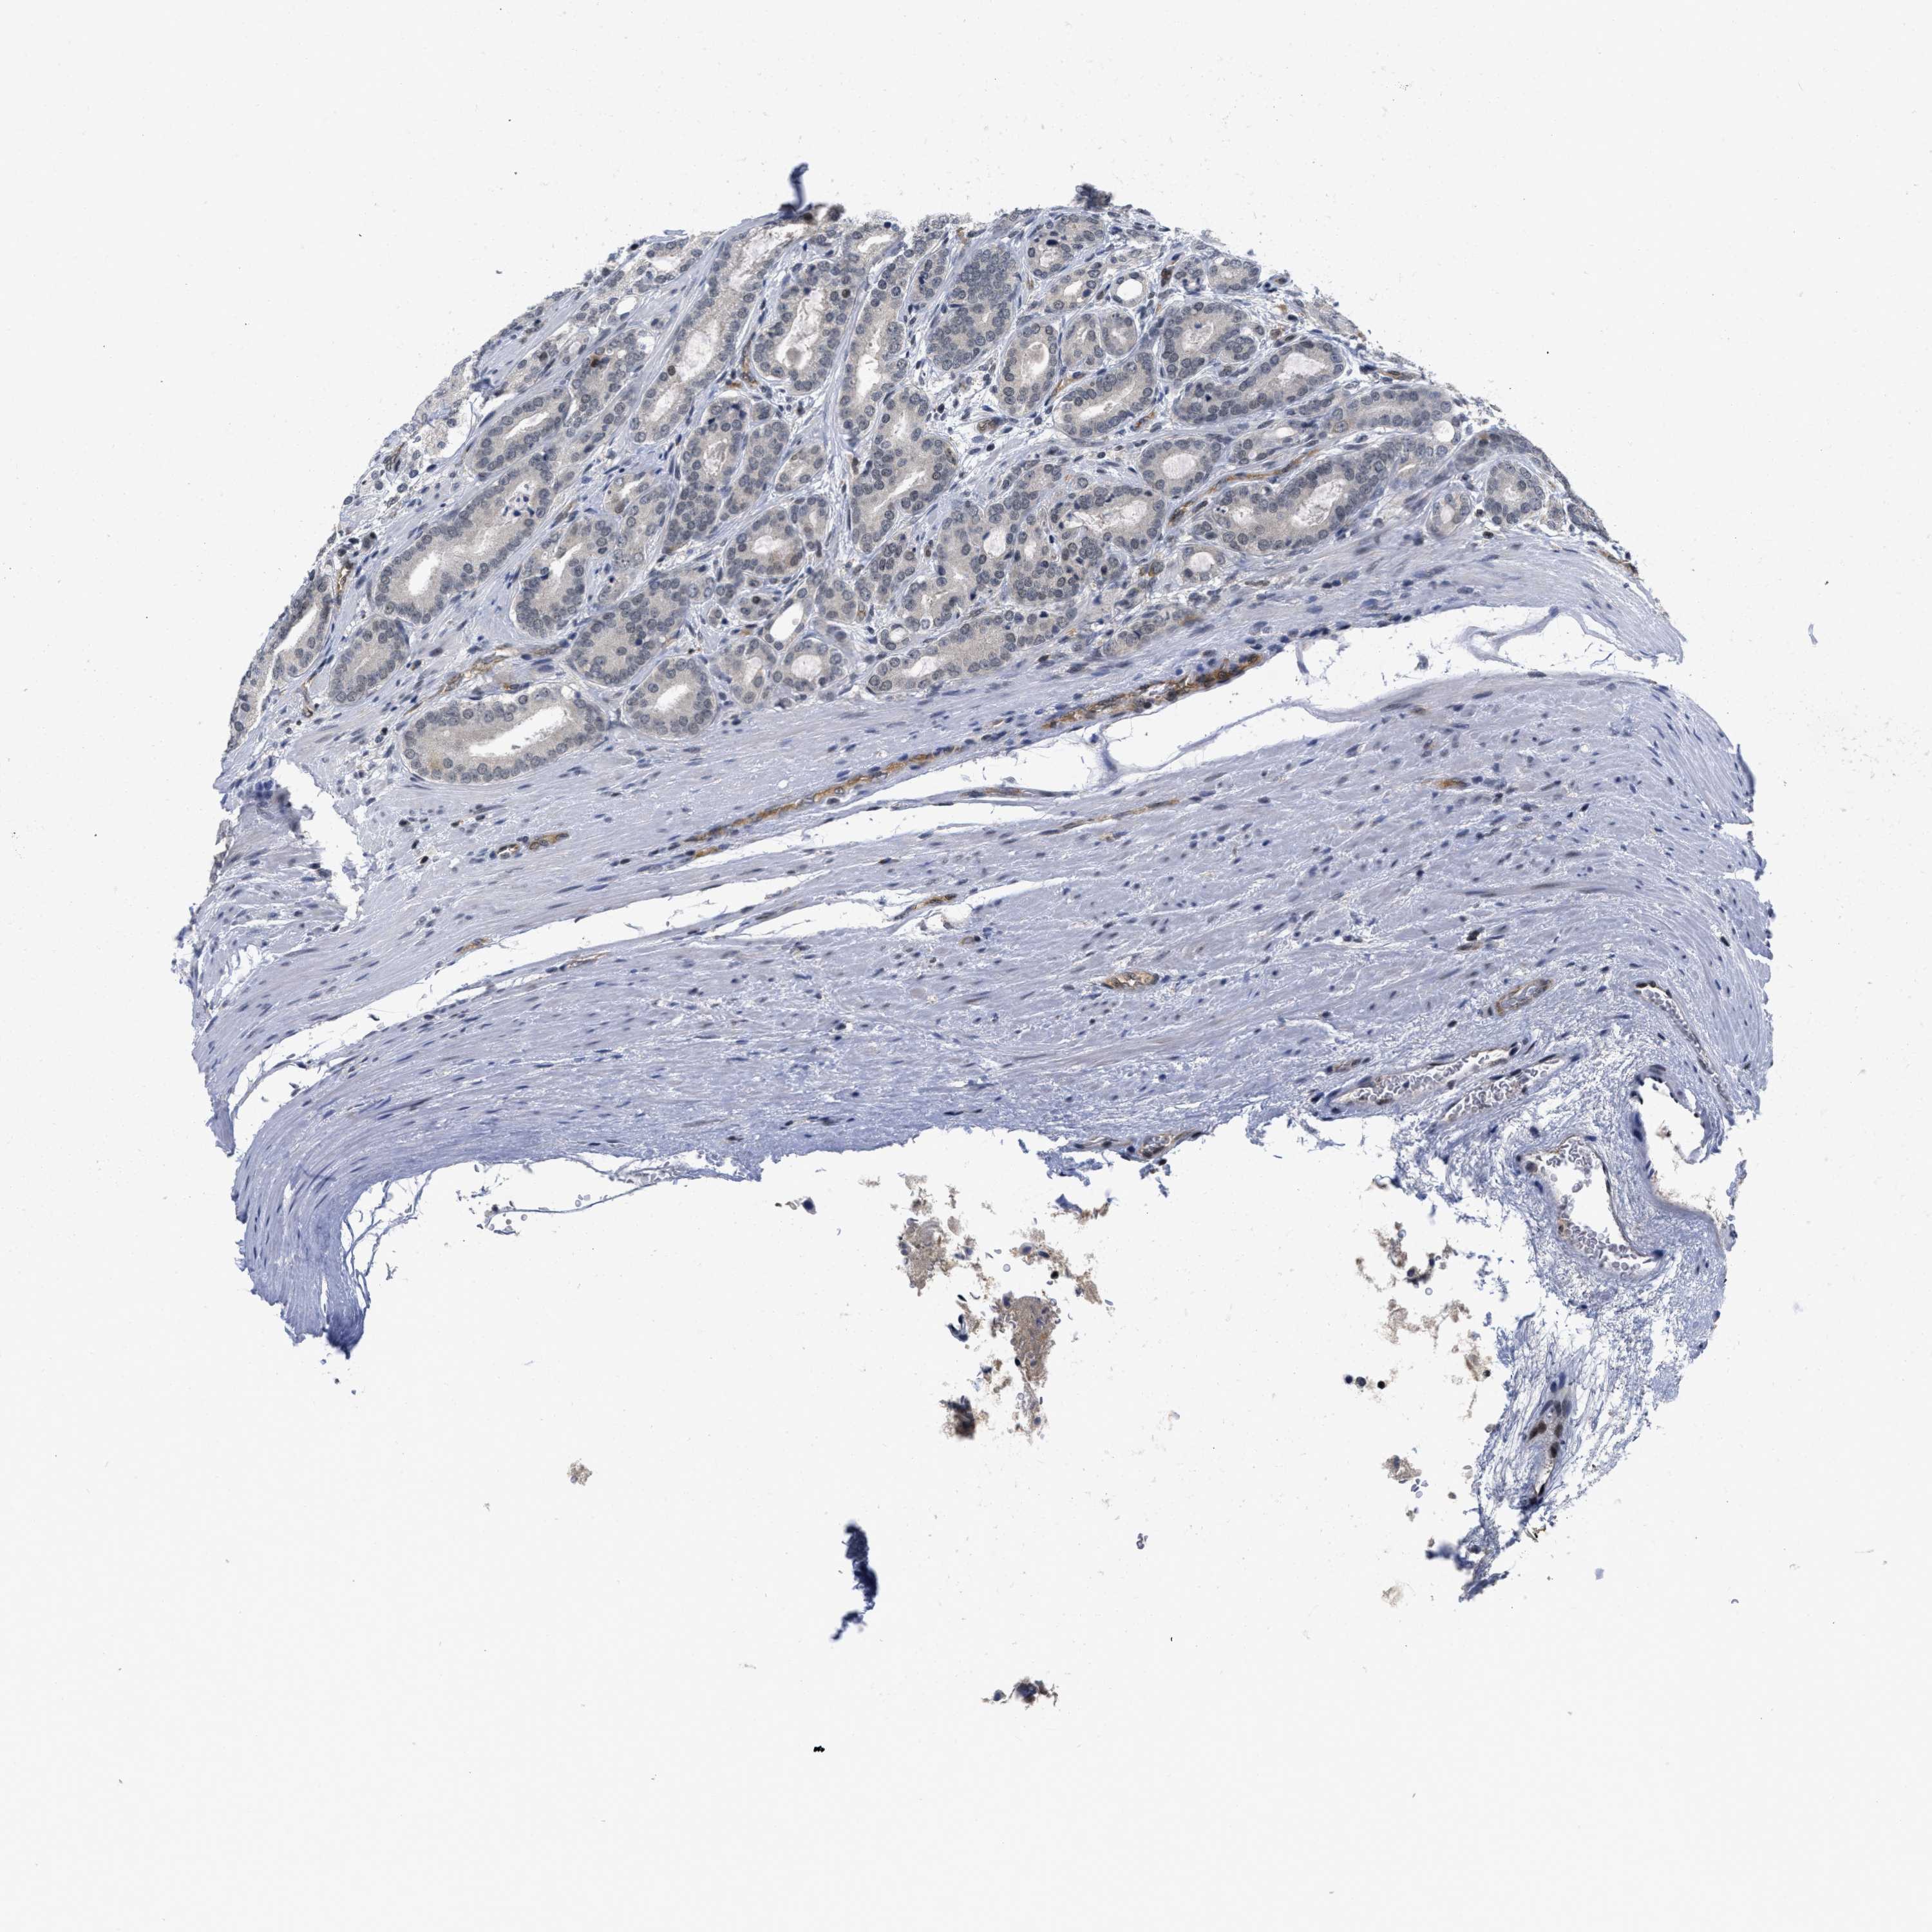

PROSTATE CANCER - Protein expressioni

A mouse-over function shows sample information and annotation data. Click on an image to view it in a full screen mode. Samples can be filtered based on level of antibody staining by selecting one or several of the following categories: high, medium, low and not detected. The assay and annotation is described here.

Note that samples used for immunohistochemistry by the Human Protein Atlas do not correspond to samples in the TCGA dataset.

Antibody stainingi

Antibody staining in the annotated cell types in the current human tissue is reported as not detected, low, medium, or high, based on conventional immunohistochemistry profiling in selected tissues. This score is based on the combination of the staining intensity and fraction of stained cells.

Each image is clickable and will lead to virtual microscopy that enables deeper exploration of all samples and also displays staining intensity scores, fraction scores and subcellular localization as well as patient and tissue information for each sample.

Antibody HPA001275

Antibody CAB017442

Staining

High

Medium

Low

Not detected

Intensity

Strong

Moderate

Weak

Negative

Quantity

>75%

75%-25%

<25%

None

Location

Nuclear

Cytoplasmic/membranous

Cytoplasmic/membranous,nuclear

Adenocarcinoma, Medium grade

Adenocarcinoma, Low grade

Adenocarcinoma, High grade